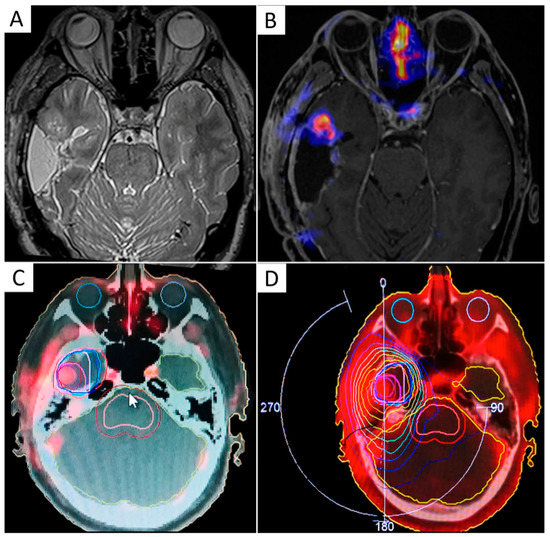

It has been shown that Hypoxia PET imaging may aid RT planning in patients with lung and head and neck cancer by safely guiding dose escalation to tumor regions with higher tracer uptake [154,155,156]. Uptake of hypoxia-targeting radiopharmaceuticals in brain tumors was found to correlate with the expression of endogenous markers of hypoxia, such as HIF-1α [157,158], and demonstrated a negative impact on survival outcomes [159,160,161]. Hypoxia PET has been used preclinically to guide radiation treatment in a rat GBM model [162]. However, only a few clinical experiences are available on patients with HGG undergoing hypoxia PET scans before and after RT, and a real PET-based treatment plan is missing in these cases [163,164] (Figure 4). Narita et al. documented reoxygenation in two patients with GBM undergoing FMISO PET scan before and after RT plus temozolomide, suggesting that the hypoxia is not spatially fixed over time and sequential hypoxia PET scans may be necessary for adaptive RT [164].

Figure 4.

Example of a volumetric modulated arc therapy (VMAT) sequential boost of radiation to hypoxia-positive recurrent GBM. T2-weighted and contrast-enhanced T1-weighted MRI sequences were acquired along with 64Cu-diacetyl-bis(N4-methylthiosemicarbazone) (ATSM) PET on a hybrid 3T PET/MR scanner, three hours after radiopharmaceutical injection (A,B). 37.5 Gy were delivered in 15 daily fractions to the surgical cavity followed by a boost of radiation (5 Gy) to the 64Cu-ATSM-positive tumor region, indicating chronic hypoxia (C,D).